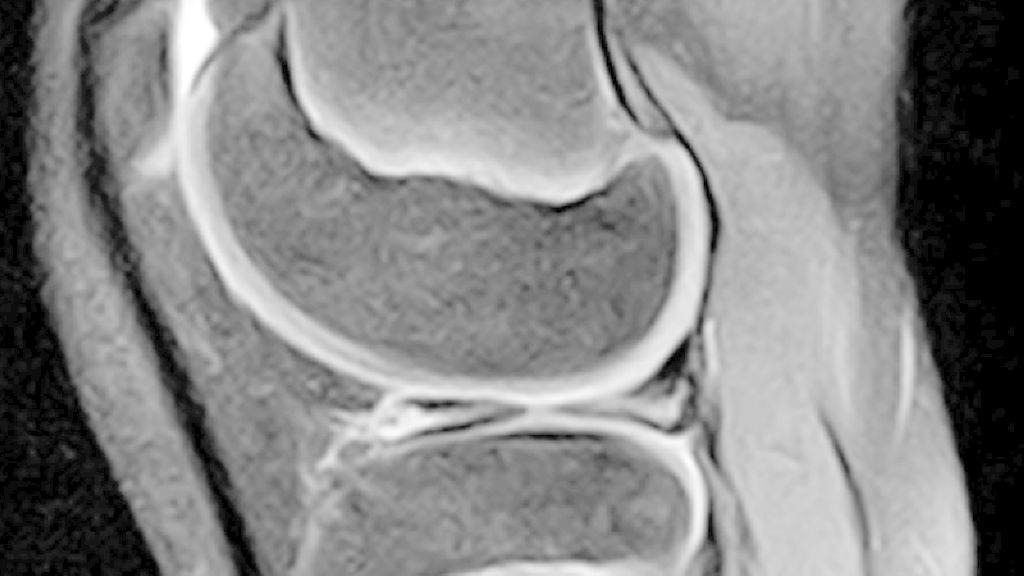

Abb. 2: MRT-Bilder des linken Kniegelenks eines 10-jährigen Jungen mit „bow-tie sign“ in der sagittalen Ansicht in T1-Wichtung

Die Magnetresonanztomografie (MRT) ist eine wesentliche Ergänzung und erlaubt eine genaue Beurteilung der Meniskusmorphologie. Als gängige diagnostische Kriterien gelten eine Breite über 15 mm in frontaler Ebene oder drei aufeinanderfolgende 5-mm-Schnitte in sagittaler Ebene mit Kontinuität zwischen anteriorem und posteriorem Horn (sog. „bow-tie appearance“) (Abb. 2).5 Gerade der inkomplette und der Wrisberg-Typ sind jedoch schwieriger zu erkennen. Hinweisend auf eine vorliegende Instabilität bzw. Hypermobilität können eine Dislokation des posterioren Meniskushorns, eine Faltung und eine höhere Signalintensität in T2 zwischen Meniskus und Gelenkskapsel sein.20,21 Neben der Morphologie gibt die MRT auch wertvolle Zusatzinformationen zu degenerativen Veränderungen und Meniskusrissen. Am häufigsten zeigen sich Horizontalrisse. Hier ist der Meniskus in ein oberes und ein unteres Blatt geteilt (Abb. 3).18